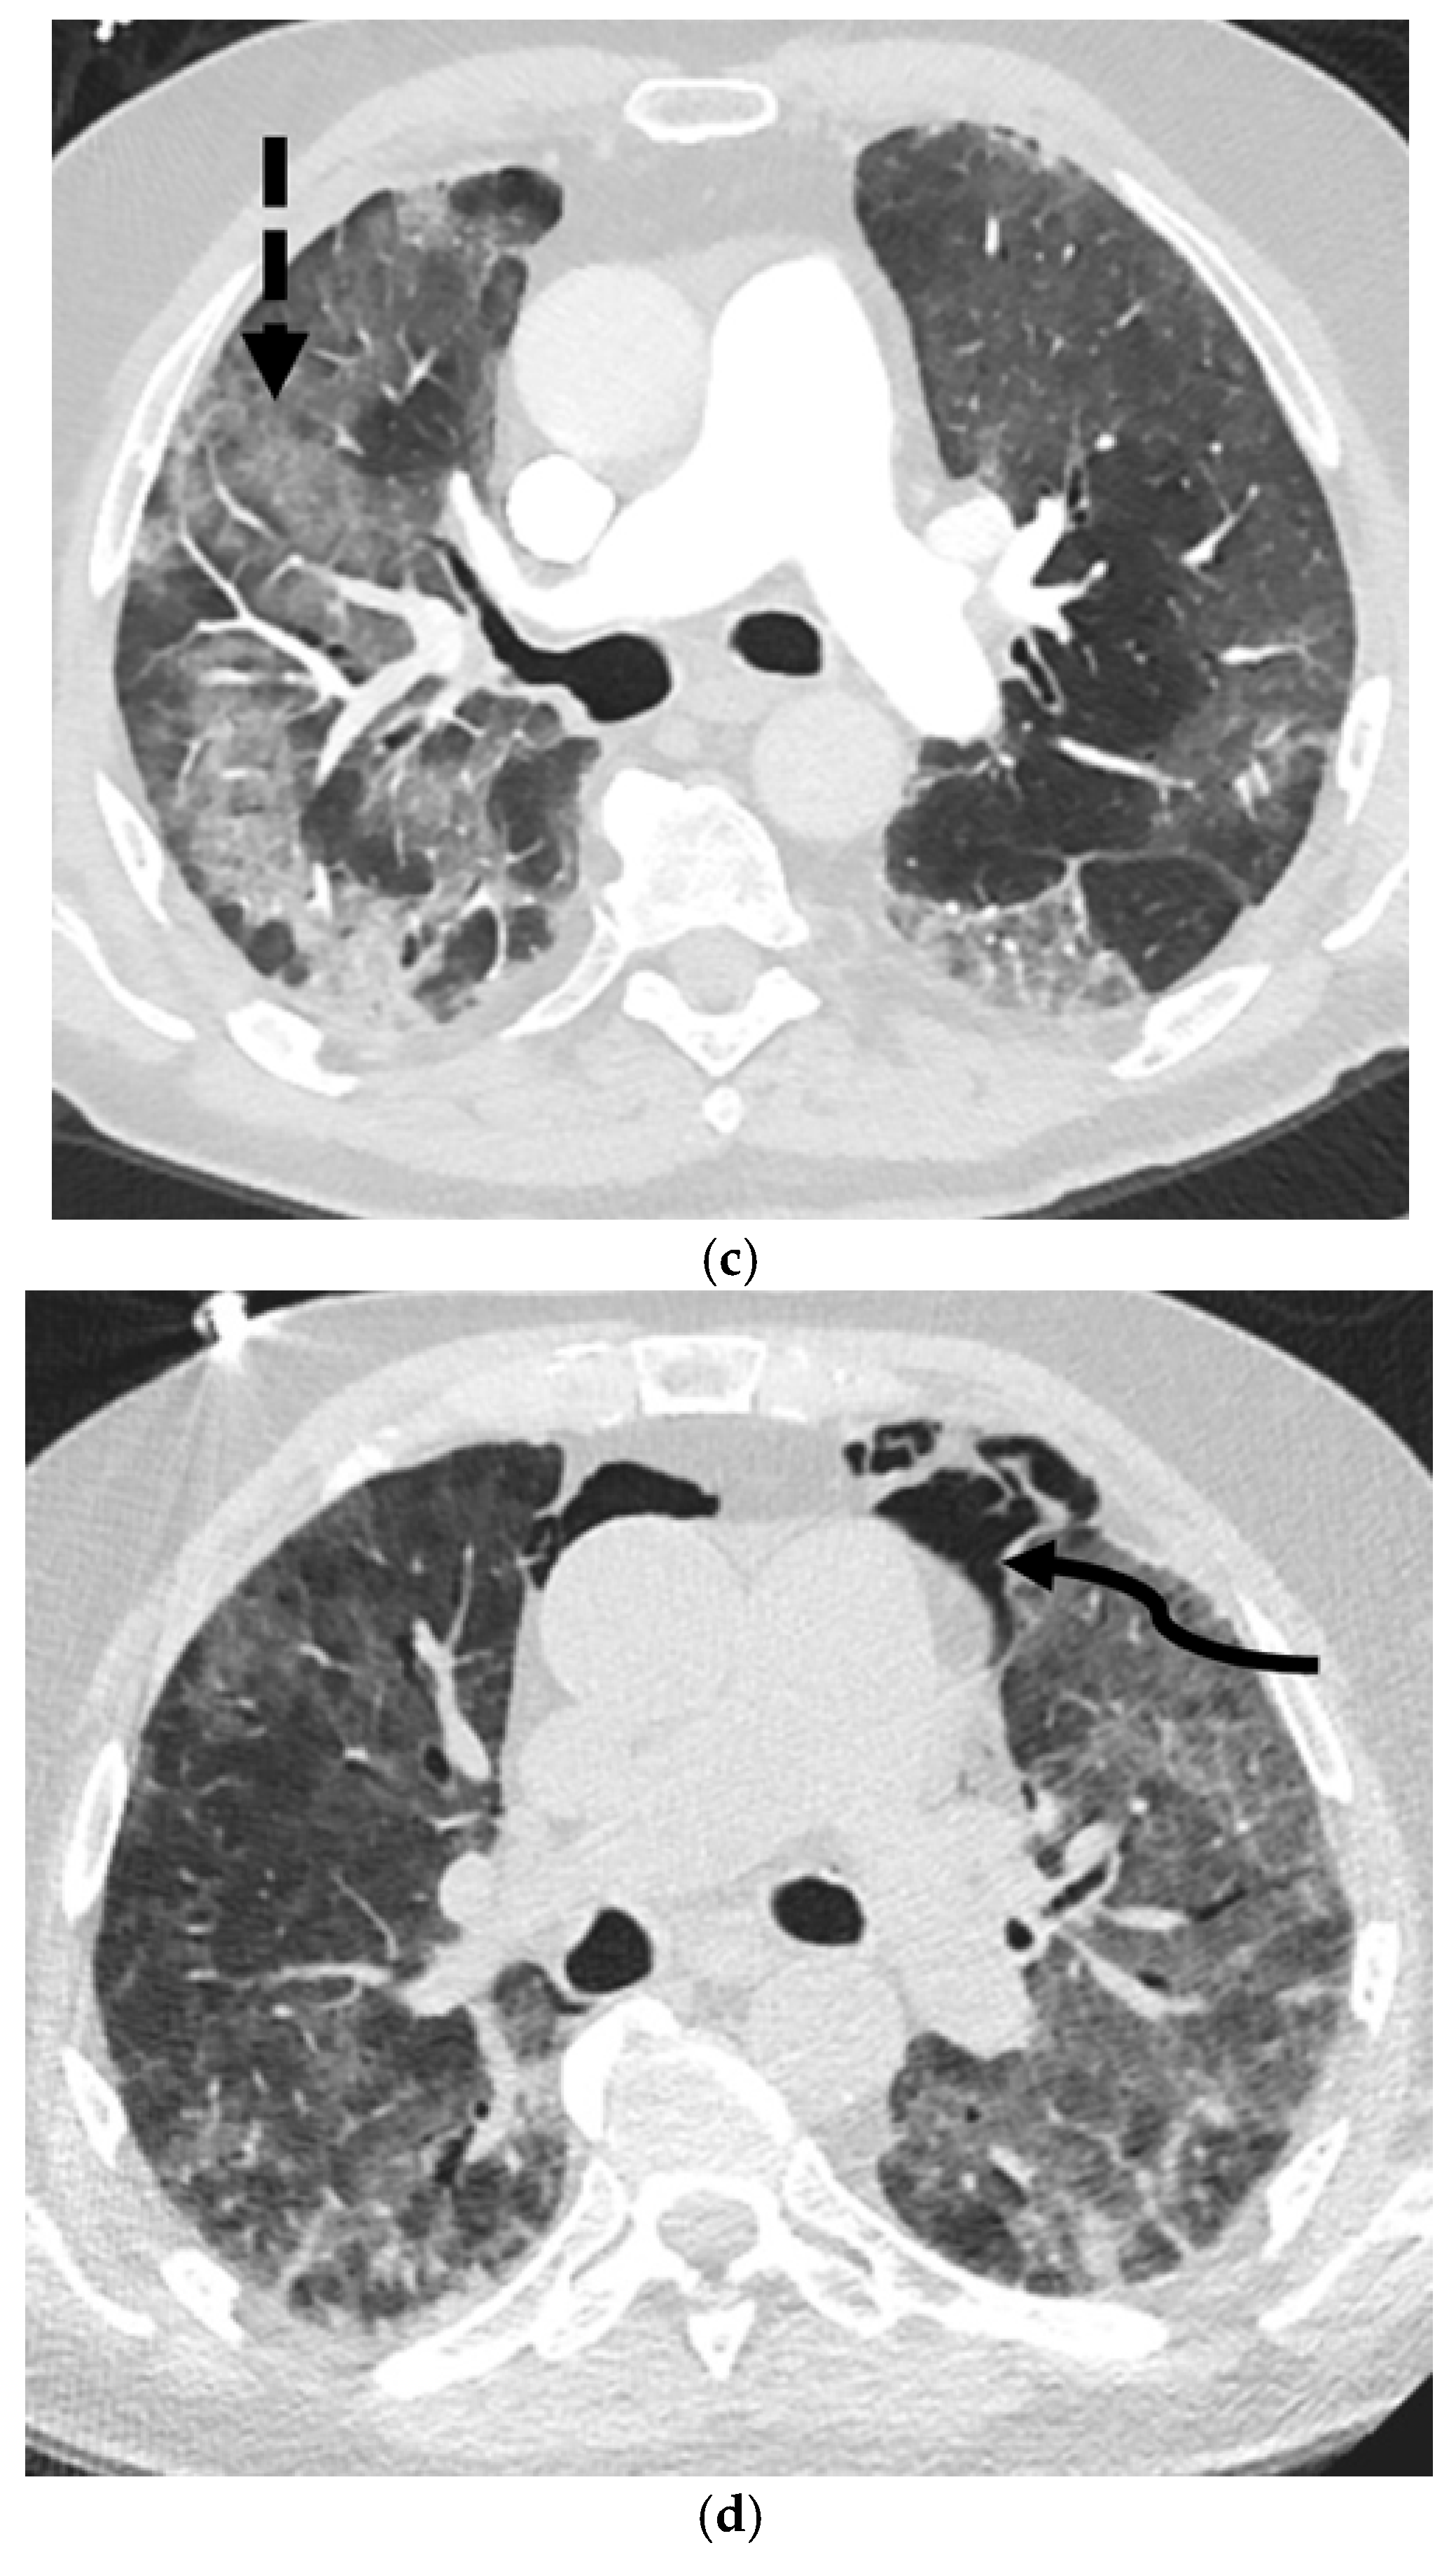

5.4.1. Idiopathic Pulmonary Fibrosis (IPF)

5.5.1. Pulmonary Langerhans Cell Histiocytosis (PLCH)

5.5.2. Lymphangioleiomyomatosis (LAM)

5.5.3. Birt–Hogg–Dubé Syndrome (BHDS)